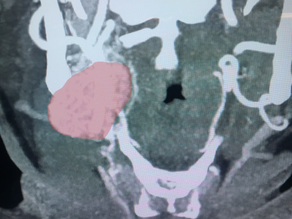

Carotid Body Tumors

Carotid Body Tumors are a form of paraganglioma similar to glomus tumors (glomus jugulare). They arise form the chemoreceptors of the carotid artery in the neck. A comprehensive team approach is required involving interventional neurovascular embolization and close collaboration with our vascular surgery colleagues to safely and completely remove these tumors.